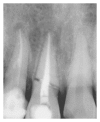

Traumatic injuries to teeth account for approximately 25% of dental conditions where a patient seeks dentist for emergency treatment. Radicular fractures are one such entity which is very challenging to address due to various complications like periodontal communication, increased mobility, and continued pulpal infection leading to necrosis. Radicular fractures in the middle third have long been considered teeth of salvage due to their unfavourable fracture pattern. During the recent years introduction of biomimetic materials has opened the horizon for saving these teeth. In the present case report a novel approach to the management of radicular fractures in the middle third has been presented.